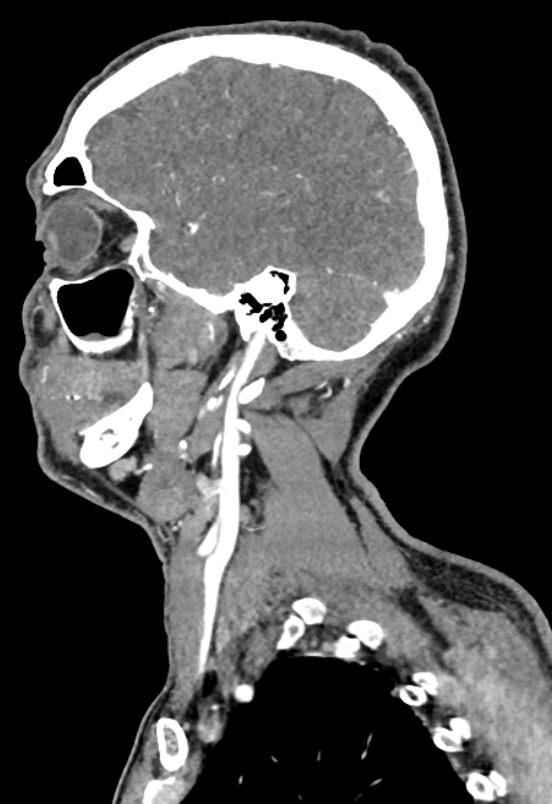

КТ сосудов шеи и головного мозга (КТ-ангиография) позволяет комплексно оценить состояние брахиоцефальных артерий и сосудов головного мозга, включая Виллизиев круг, передние средние и задние мозговые артерии. С помощью КТ-ангиографии можно выявить аномалии развития сосудов (в том числе, аневризмы артерий головного мозга, артериовенозные мальформации), патологические извитости, участки сужения и полной закупорки просвета сосуда. КТ-ангиография покажет утолщение стенки артерии, точную локализацию атеросклеротической бляшки, стенозы и окклюзии просвета сосудов, степень функционирования Виллизиева круга, что бывает особенно важно при планировании оперативного вмешательства и для оценки эффективности хирургического лечения.

В нашей клинике КТ сосудов шеи и головного мозга выполняется на современных мультиспиральных компьютерных томографах экспертного уровня TOSHIBA AQUILION. Для визуализации сосудистой системы в обязательном порядке проводится контрастное усиление. Для этого в вену пациенту вводится йодсодержащий контрастный препарат, который хорошо поглощает рентгеновские лучи и обеспечивает яркую видимость сосудистой сети на фоне окружающих тканей.

Высокотехнологичное оборудование последнего поколения обеспечивает высокую точность и контрастность изображений, благодаря чему получаются снимки и трехмерные модели сосудистой системы высокого качества. Увеличенное количество детекторов позволяет производить одномоментно множество послойных снимков, что значительно сокращает время исследования и минимизирует уровень лучевой нагрузки на организм пациента.